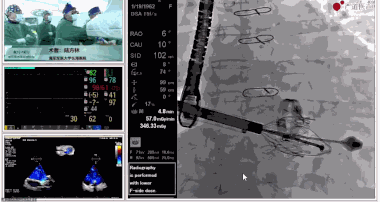

▲瓣膜植入后釋放的過(guò)程

▲瓣膜植入后三維超聲影像

▲瓣膜植入后右心室造影

在手術(shù)直播中瓣膜植入過(guò)程不到10分鐘,手術(shù)獲得圓滿(mǎn)成功,充分體現(xiàn)徐志云、陸方林團(tuán)隊(duì)技術(shù)精湛,團(tuán)隊(duì)協(xié)作默契及器械的優(yōu)越性。

該例患者返回后當(dāng)天拔除氣管插管,生命體征穩(wěn)定,恢復(fù)良好。此次會(huì)議不僅有最前沿的學(xué)術(shù)講座,更有3D體驗(yàn)般的手術(shù)直播,為大家第一視角直觀(guān)呈現(xiàn)領(lǐng)域新技術(shù)、新策略、新思路。